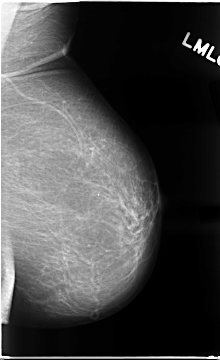

C_0073_1.RIGHT_MLO

RIGHT_MLO LINES 4712 PIXELS_PER_LINE 2648 BITS_PER_PIXEL 12 RESOLUTION 50 OVERLAY